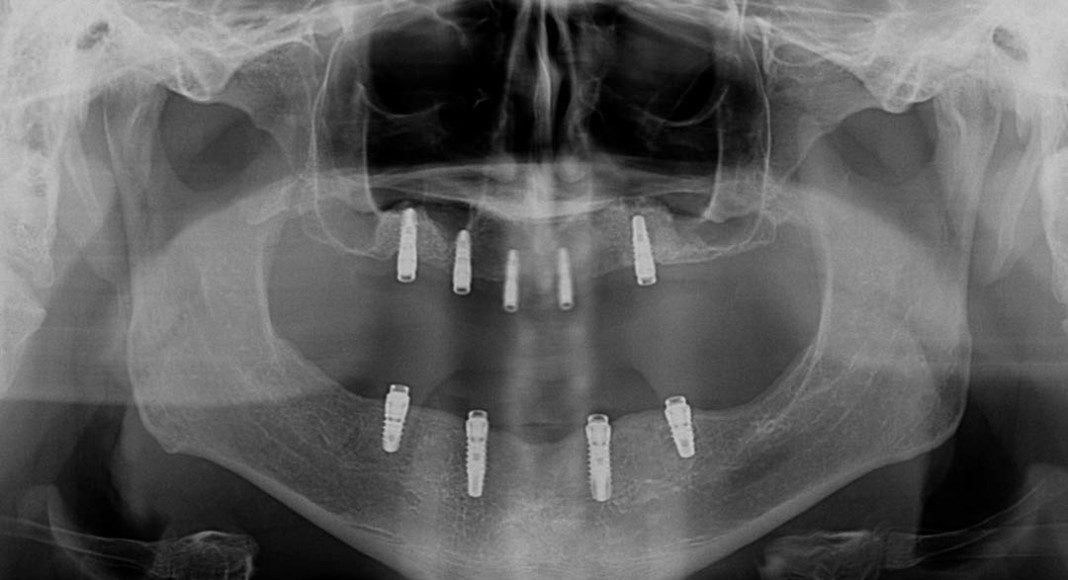

A screen shot of the panoramic view from a CT scan. The patient has almost no bone in the upper jaw. In order to have upper implants, he will need sinus and onlay bone grafting to increase bone height and width (total bone volume).